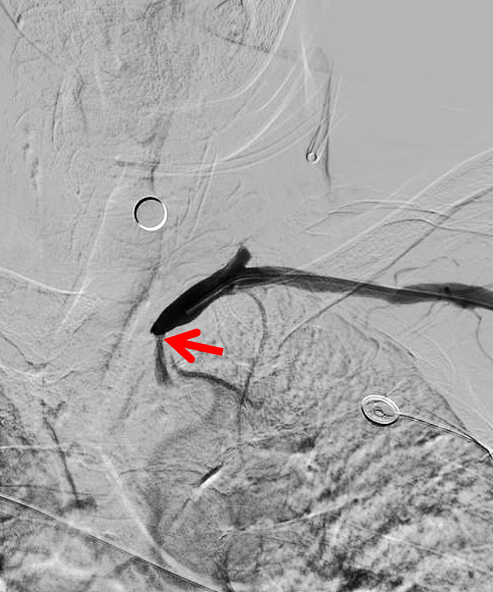

NeuronMax头端顺应性良好【白箭头】,球囊扩张支架充分